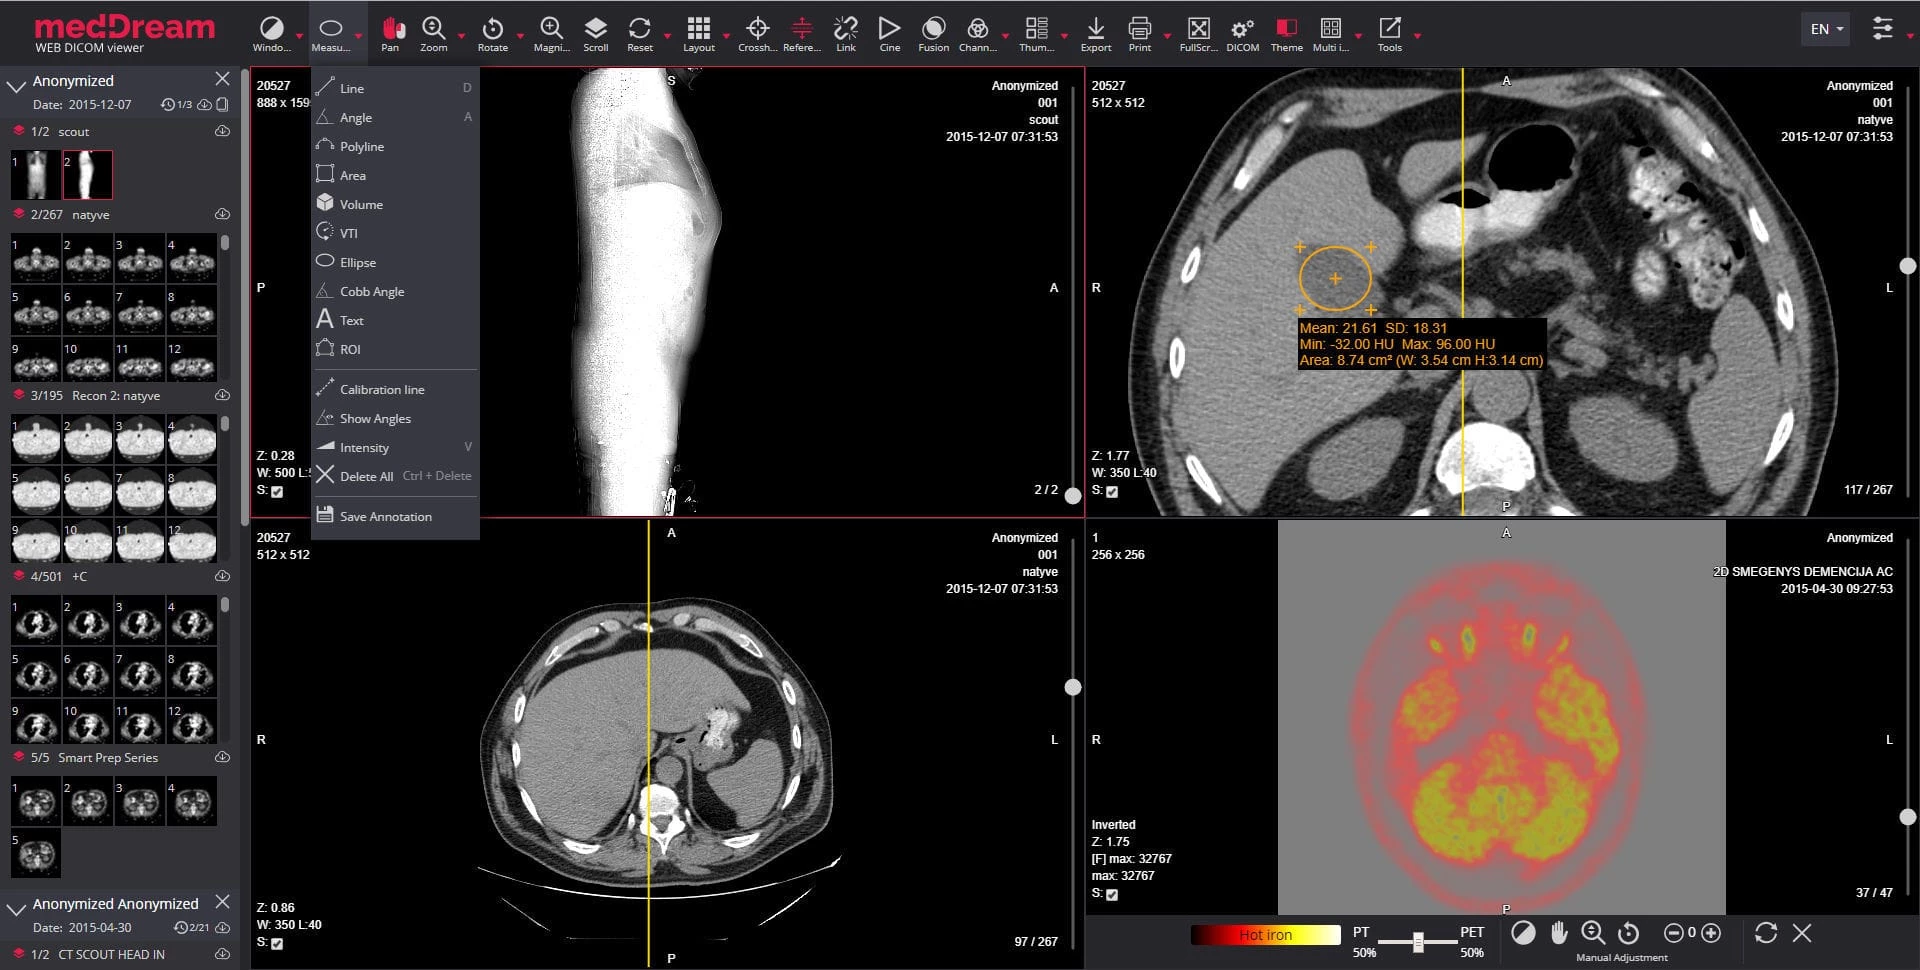

After we found vulnerabilities in one of the most popular DICOM libraries, we started to focus on a popular PACS implementation: Softneta MedDream. MedDream is one of the more popular viewer and PACS applications, boasting many DICOM and web management capabilities.

The MedDream Viewer and PACS server, showing a medical image sent over DICOM.

Our goal this time was not finding vulnerabilities in the DICOM parsing primitives necessarily, instead we aimed to find vulnerabilities in the platform, which might be exposed on internet-facing installations. Since MedDream exposes a few web-based endpoints, mainly the web-based DICOM viewer and the PACS management platform, we started our research there.